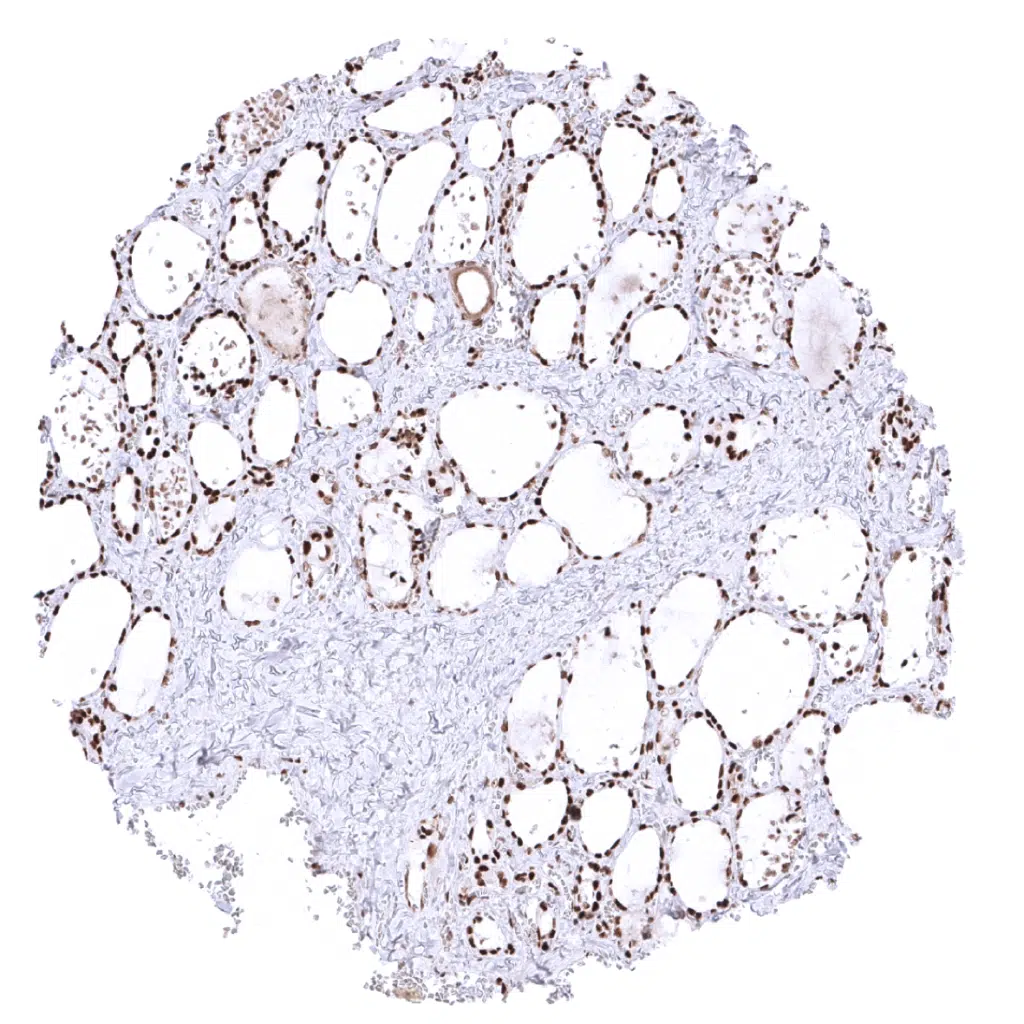

Kidney, cortex